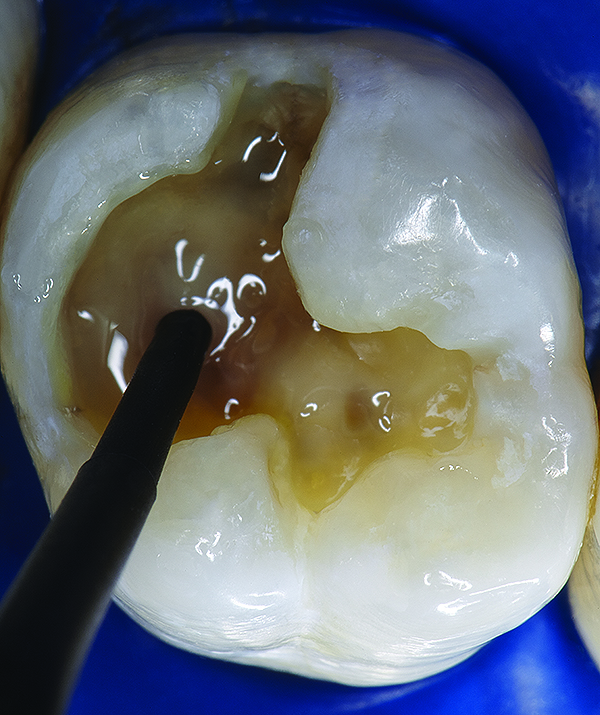

Figure 10. A self-etching, light-cured adhesive (G-aenial™ Bond, GC America) was applied to the prepared enamel and dentin surfaces using a disposable applicator and allowed to dwell for 10 seconds.

Figure 10